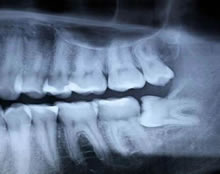

The dentist will be able to assess whether there is sufficient room for the teeth to come through by taking an x- ray which will show the position of the root. Once the x-rays have been taken, the dentist will be able to tell how easy or difficult it will be to remove the tooth. The dentist will then determine whether the tooth should be taken out at the Dental Practice or by a Specialist Oral Surgeon.